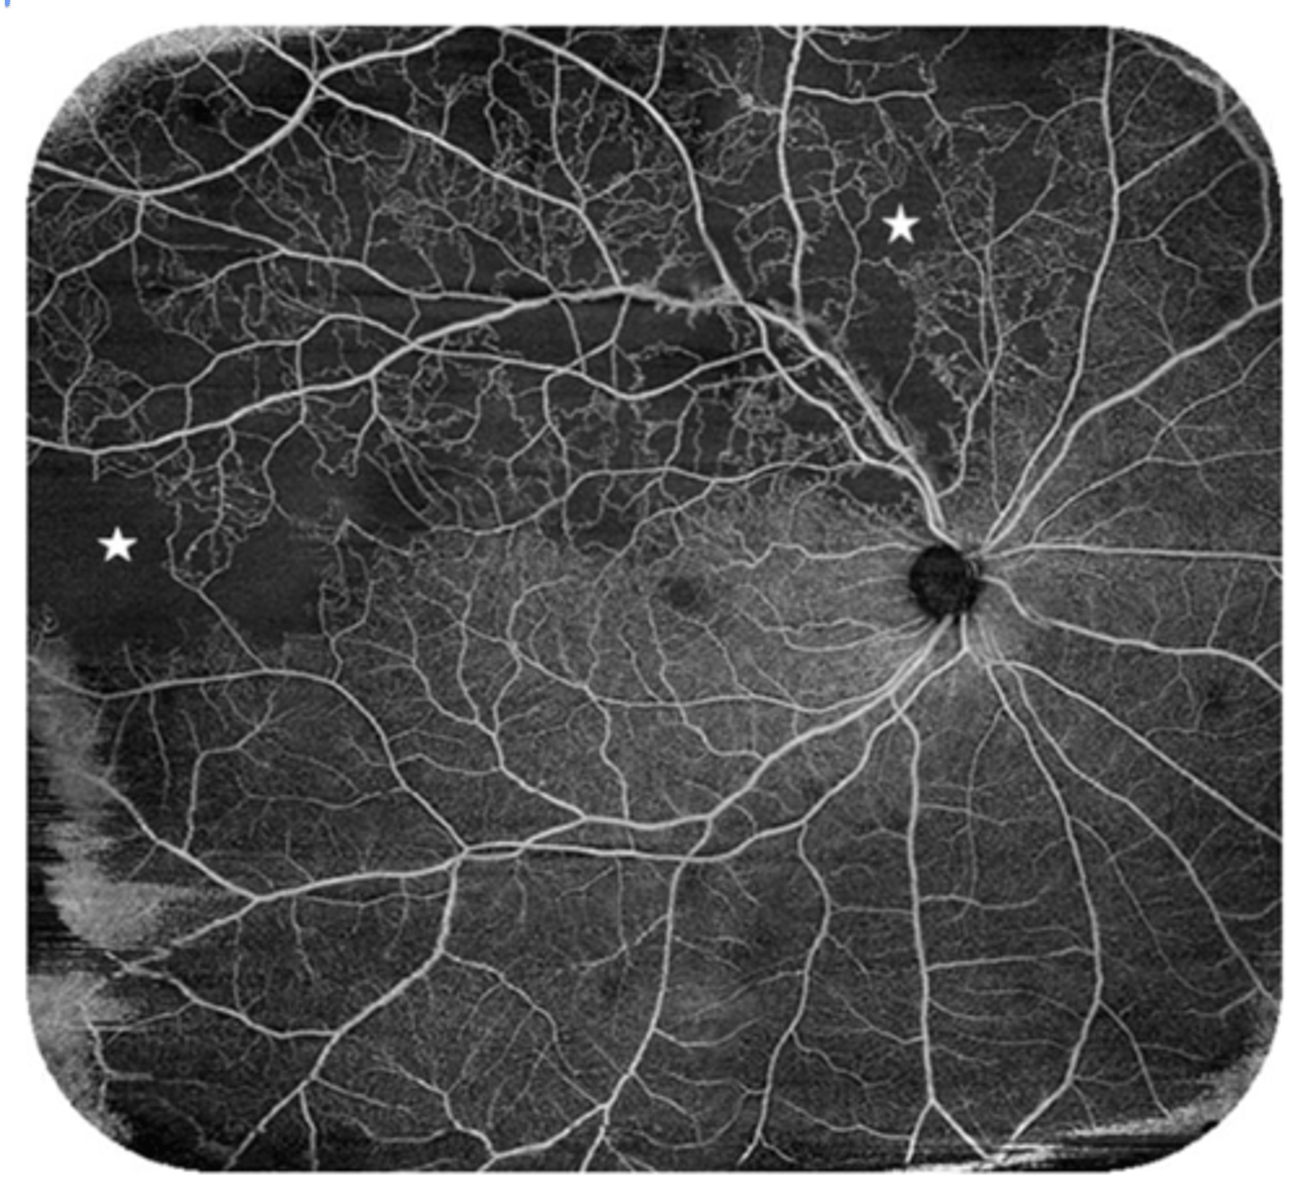

What is the only definitive way to tell the difference between non-ischemic and ischemic venous occlusions?

FANG → hard to do early because too much blood it covers everything

may need to use OCT to see if there's macular edema

image - ischemic CRVO that shows FANG (low perfusion)

Ischemic CRVO has lost at least how much retinal perfusion?

at least 10 DD

What does CRVO look like on OCTA?

dark areas = non-perfusion (capillary dropout)